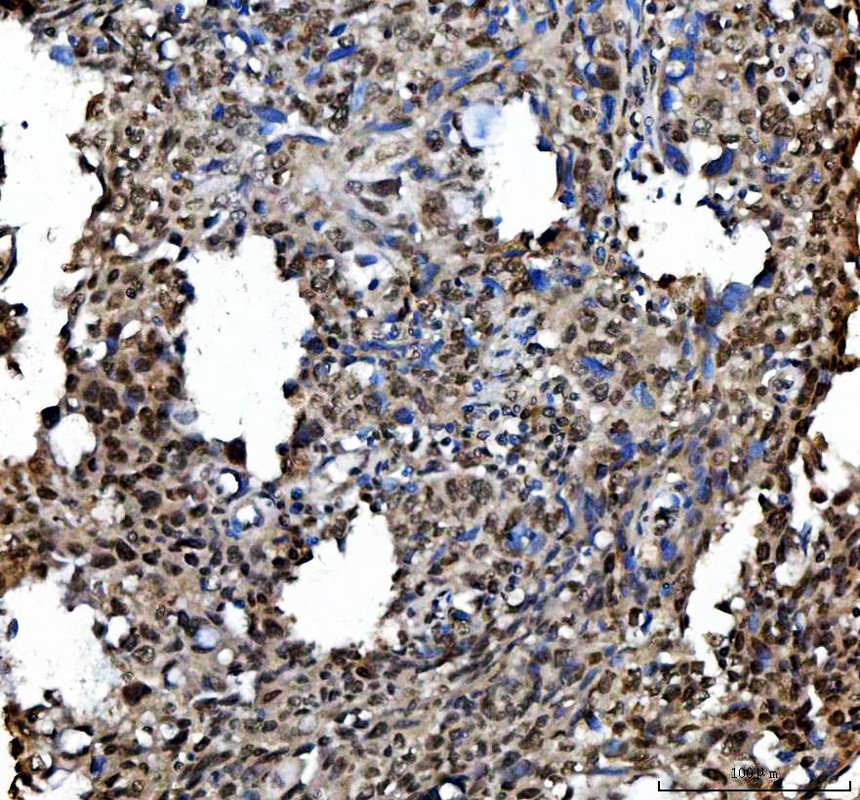

IHC analysis of Ki67/MKI67 using anti-Ki67/MKI67 antibody (PB9026).

Ki67/MKI67 was detected in a paraffin-embedded section of human lung cancer tissue. The tissue section was incubated with rabbit anti-Ki67/MKI67 Antibody (PB9026) at a dilution of 1:200 and developed using HRP Conjugated Rabbit IgG Super Vision Assay Kit (Catalog # SV0002) with DAB (Catalog # AR1027) as the chromogen.